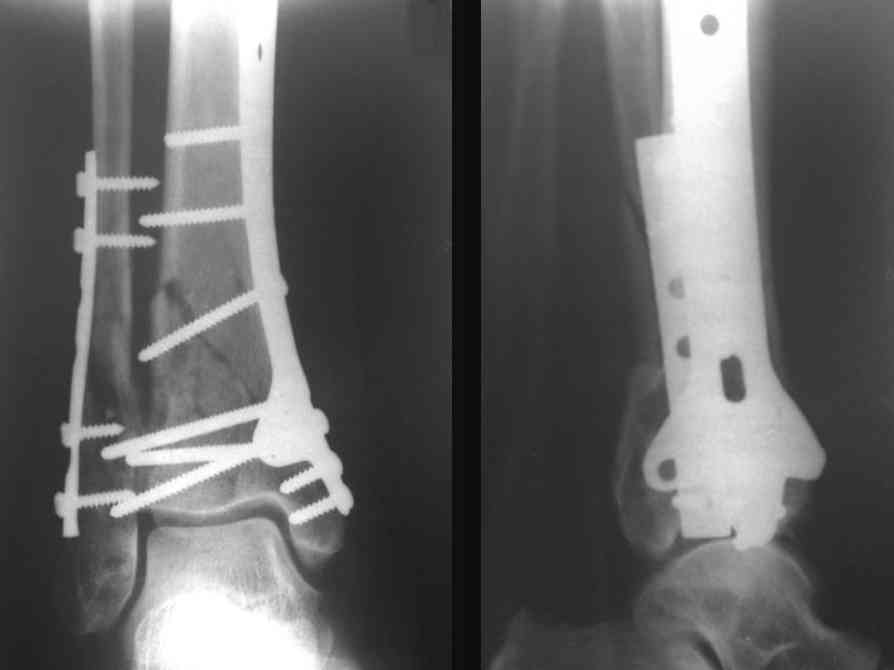

Послала ещё два снимка, если не пройдут, пошлю ещё. Дрягин. Если есть вопросы, готов ответить.

На рентгенограммах типичный перелом пилона по типу С-3. есть опыт до 100 открытых опреаций у нас в клинике. 20 примерно в год. Принцип один -все внутрисуставные переломы нуждаются в открытой репозиции и внутренней стабильной фиксации. При поступлении КТ не надо, так как получается только нагромождение костей. Истинной картины нет. Главное восстановить длину малоберцовой кости - это ключ к успеху. При поступлении меньше всего надо думать о сосудистых расстройствах, т.к. сама операция и репозиция даже сначала частичная даёт улучшение сосудитых нарушений. Причём очень быстро. Операция в 2этапа. При поступлении доступ позади наружной лодыжки, причём обязательно. После этого репозиция малоберцовой кости и фиксация пластиной 1/3 трубки под винт 3,5. Дренаж и любой аппарат наружной фиксации. Затем после спадения отёка на 5-7-10 день аппрат снимается и дугообразный разрез спереди от медиальной лодыжки 10-12 см. Главной чтобы расстояние между 1 и вторым разрезом было не меньше 7-8 см. Тогда не будет некрозов лоскутов. Таранная кость используется как матрица на неё укладываются отломки и фиксируются пицами. Ренг-контроль. Отломки лежат все отдельно, но ничего не высыпется. При переломах С-3 всегда нужна костная пластика (из крыла). Фиксация пластиной лист клевера простой или LCP. Гипс не нужен. Дренаж до 48 часов. Операция длится 3-4 часа обязательно без жгута. Посылаю примерно такой же случай.

Посмотрим вроде прошло если понравится напишите расскажу как это сделать.По принципам АО кстати при поступлении сначала восстанавливают длину малоберцовой кости фиксируют пластиной 1/3 трубки потом накладывают аппарат наружной фиксации и через 7-10 дней открыто восстанавливают большеберцовую кость.С уважением Дрягин